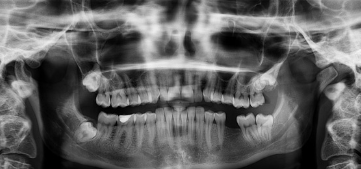

임플란트란 무엇인가요?

임플란트란 치아가 빠졌을 때 인공치근(임플란트)을 잇몸 뼈에 식립해 자연치아처럼 기능하게 만드는 치료입니다.

자연치에 가까운 기능과 외관을 제공하기 때문에 많은 분들이 임플란트를 선택하고 있습니다.

특히 추가로 뼈이식등의 시술이 필요한 경우 비용이 추가 발생할 수 있으니 참고해주세요!(저는 뼈이식비용까지 들었었네요ㅜㅜ)

- 뼈이식, 잇몸치료 등의 추가 치료 유무